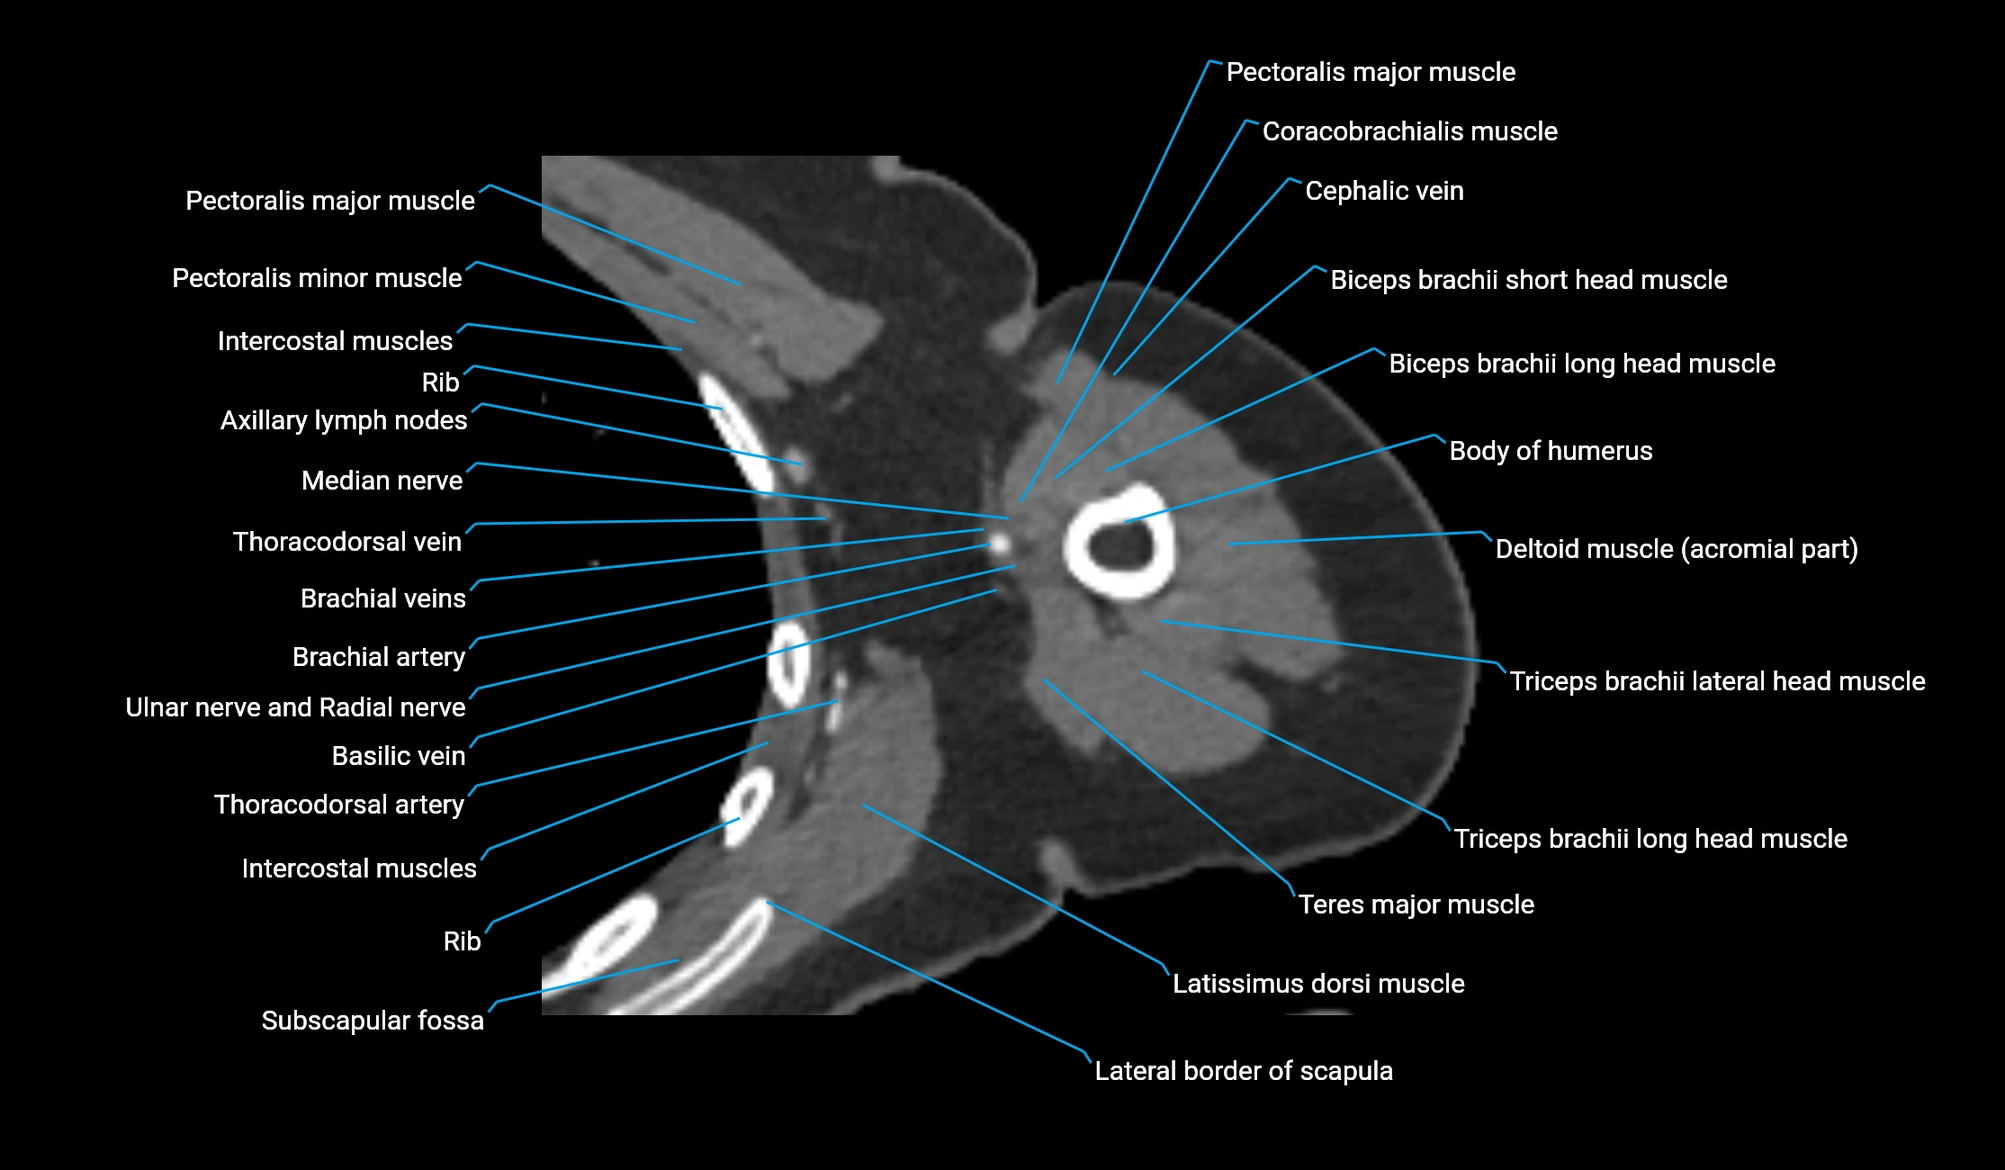

- Axillary lymph nodes

- Basilic vein

- Brachial artery

- Cephalic vein

- Coracobrachialis muscle

- Lateral border of scapula

- Lateral head of triceps brachii muscle

- Long head of biceps brachii muscle

- Long head of triceps brachii muscle

- Median nerve

- Pectoralis major muscle

- Pectoralis minor muscle

- Short head of biceps brachii muscle

- Subscapular fossa

- Teres major muscle

- Thoracodorsal artery

- Triceps brachii muscle